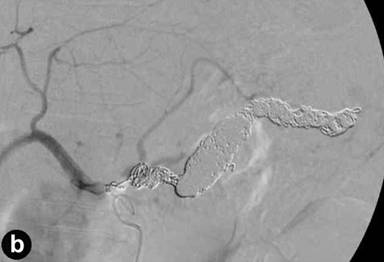

An emergency intervention was then carried out. Angiography clearly revealed a fusiform aneurysm of the middle-distal splenic artery and narrowing of the proximal splenic artery (Figure 4a). All parts of the splenic artery were successfully coil-embolized (Figure 4b). Twenty days later, intervention for dissection of the celiac artery was performed. The celiac artery including the false lumen was successfully coil-embolized (Figure 4c). The patient has since shown no recurrence of the epigastric pain or melena.

Figure 4. a. Angiography of the celiac artery clearly showing the narrowing of the proximal splenic artery (small arrow) and a fusiform aneurysm of the middle-distal splenic artery (large arrow). b. Angiography of the celiac artery showing that all parts of the splenic artery were successfully coil-embolized. c. Lateral angiography of the celiac artery showing that the celiac artery including the false lumen was successfully coil-embolized. |